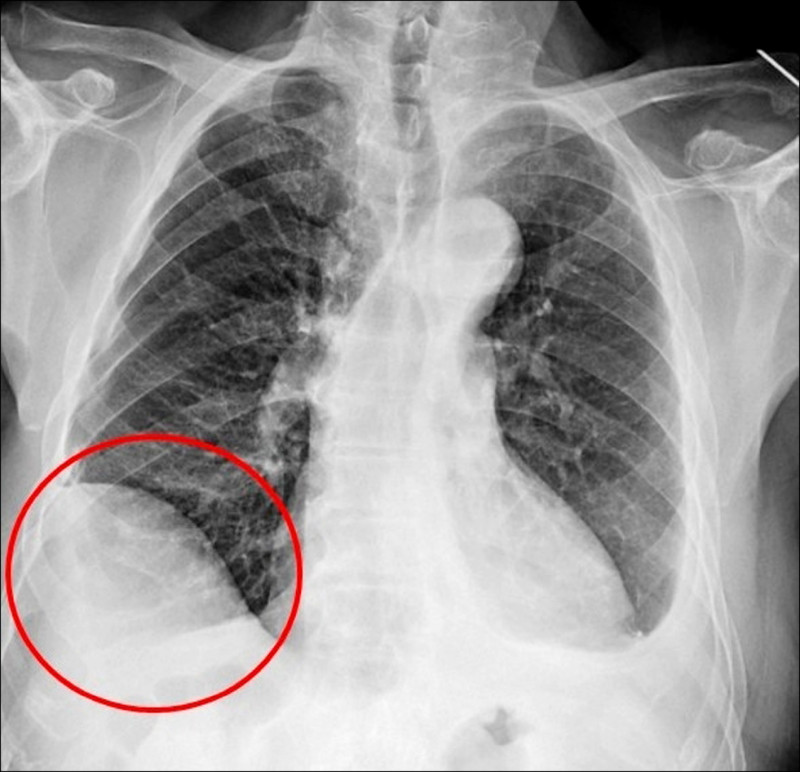

75歲吳先生因肝臟細胞癌接受治療,沒想到又發現右下肺有1顆約1.2公分的腫瘤,因疑似肺癌轉介到胸腔及心臟血管外科,醫療團隊評估後,決定進行手術切除,但因患者過去有車禍導致橫膈膜受傷,讓手術預期難度提高,決定採用健保給付的達文西機器人手術執行肺結節切除,順利切除腫瘤,並在術後第3天就出院返家休養。

仁愛長庚合作聯盟醫院胸腔及心臟血管外科主任廖啟耀表示,肺腫瘤手術在台灣十分普及且發達,但部分患者會讓醫師預期手術難度提高,其中以過去有外傷經歷、曾接受過胸腔手術、肺臟腫瘤接受過放射性治療的病人最為常見,這類患者常見的手術困難度為解剖構造的改變,常因為胸腔發炎反應的影響,讓肺臟與周遭肋膜產生沾黏,同時血管的方向也更難分辨,對執行手術醫師而言,是一項困難的挑戰。

廖啟耀表示,患者因外傷使手術困難度上升,過往使用傳統開胸手術或胸腔鏡手術在類似的病人,常因為分沾黏導致肺破損,需要較長的恢復時間,但是在進行達文西手術的過程中,不只術中沒有發生因為分沾黏常見的出血、肺破損等問題,患者在術後第2天便可拔除胸腔引流管,恢復順利。